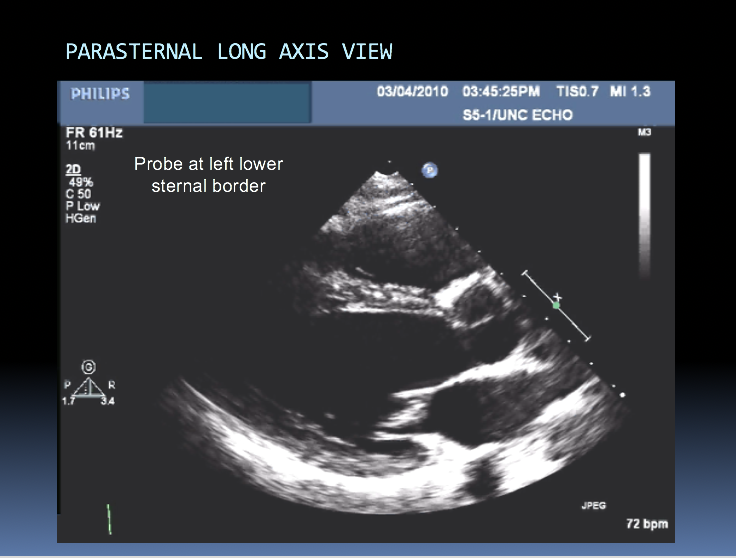

Have 2 primary probe positions, with multiple angulations (multiple ultrasonic beams are transmitted from transducer through a wide arc). The returning signals are integrated to produce 2D images of the heart on a video monitor.

Identify the chambers shown in this image: